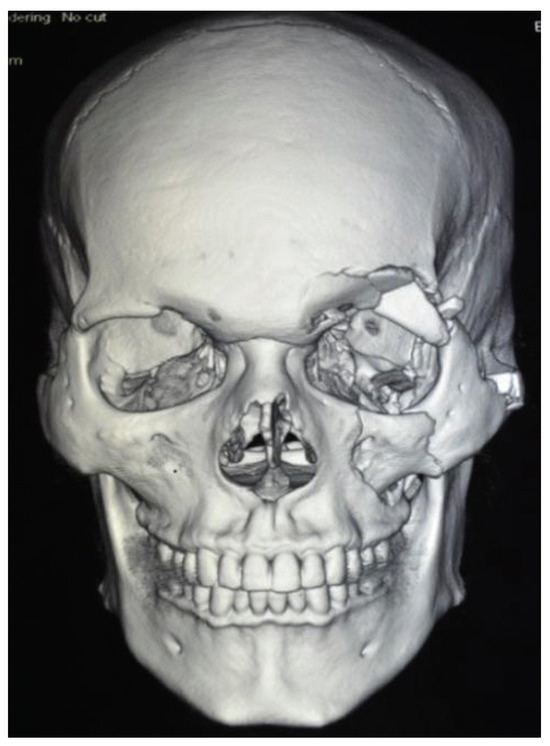

The exposure of the facial skeleton to injuries has alarmingly increased in India due to over population, poor road conditions, and increasing number of speedy automobiles. Among all bones of the facial skeleton, the zygoma and the mandible are highly accessible to the traumatic elements. In response to heavy forces, zygomatic bone gets separated from its neighboring bones at or near the respective sutures. “Zygoma” is a prominent bone in the face, when viewed frontally, semilaterally and laterally through bird’s eye and worm’s eye view. Term “zygoma” means a yoke which unites structures and is a major contributor to the orbit. The four articulations of zygoma with facial bones are of aesthetic significance in restoration of facial width and lateral projection and in treating maxillofacial trauma. These disarticulations may lead to fractures of zygomaticomaxillary complex (ZMC), zygomatic complex, or fractures of orbitozygomatic region. Sphenozygomatic junction was the important landmark with respect to zygomatic fractures reduction (especially in laterally displaced fractures). The alignment of the zygoma with the greater wing of the sphenoid in the lateral orbit is critical for determining adequate reduction of zygomatic fractures. ZMC fractures are associated with orbital volume change. Surgical reduction of the three points that makes up the buttresses also helps ensure proper alignment of the zygoma and proper reduction of other facial fractures present.

Point fixation is done at frontozygomatic (FZ) suture and zygomaticomaxillary buttress: three-point fixation is done at FZ, zygomaticomaxillary buttress, and infraorbital rim; four-point fixation of zygoma has been advocated at FZ, zygomaticomaxillary buttress, infraorbital rim, and zygomatic arch; and five-point fixation will include phenozygomatic suture according to the latest fixation techniques. Though fixation is adequate and even if fixed in two points, other areas need to be explored for reduction. Sphenozygomatic suture, zygomatic arch, and infraorbital rim need expertise to explore the fracture. Fractures of zygomatic complex present challenges in diagnosis and reconstruction for maxillofacial surgeons.

Edema that rapidly sets in makes clinical examination difficult, since the physical findings are masked. Successful reductions are often difficult to evaluate clinically because of great amount of swelling. Numerous techniques have been described to reduce zygoma fractures. The position of the fragment is usually confirmed by palpation; however, digital exploration and crepitus are unreliable guide in some cases. The assessment of the treatment of zygomatic complex fractures has also been done by visualization methods such as computed tomography (CT), photographs, and radiographs. The photographic comparison of the face by frontal, profile, three-quarter, bird’s, and worms eye views are to be done. These are useful for determining the malar symmetry, position of the globe (enophthalmos, pupillary height), eyelid position and form, facial width, and obvious scars [1].

Patients with isolated unilateral displaced ZMC fracture with orbital volume change are included in the study. Study was done for a time period of 1 year from September 2013 to September 2014 in Sri Ramachandra University, Chennai. All the patients had mid-facial trauma, acquired in road traffic accident. Among 248 trauma cases, 63 patients had zygomatic fractures.

Inclusion criteria are adult patients (patients with completed growth periods, older than 18 years) with unilateral displaced ZMC fractures (tetrapod fracture) with or without associated mandibular fractures.